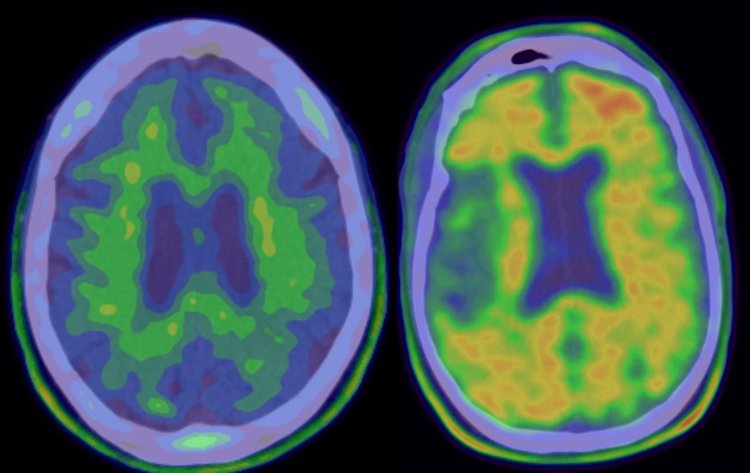

Scansioni PET: a sinistra una scansione 'negativa' (senza patologia di Alzheimer); a destra una scansione 'positiva' di un paziente eleggibile per lo studio clinico del Solanezumab. (Fonte: Columbia University Medical Center)